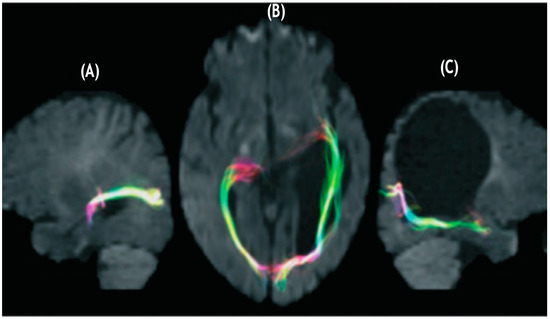

- Lennartsson, F.; Holmström, L.; Eliasson, A.C.; Flodmark, O.; Forssberg, H.; Tournier, J.D.; Vollmer, B. Advanced fiber tracking in early acquired brain injury causing cerebral palsy. AJNR Am. J. Neuroradiol. 2015, 36, 181–187. [Google Scholar] [CrossRef] [PubMed]